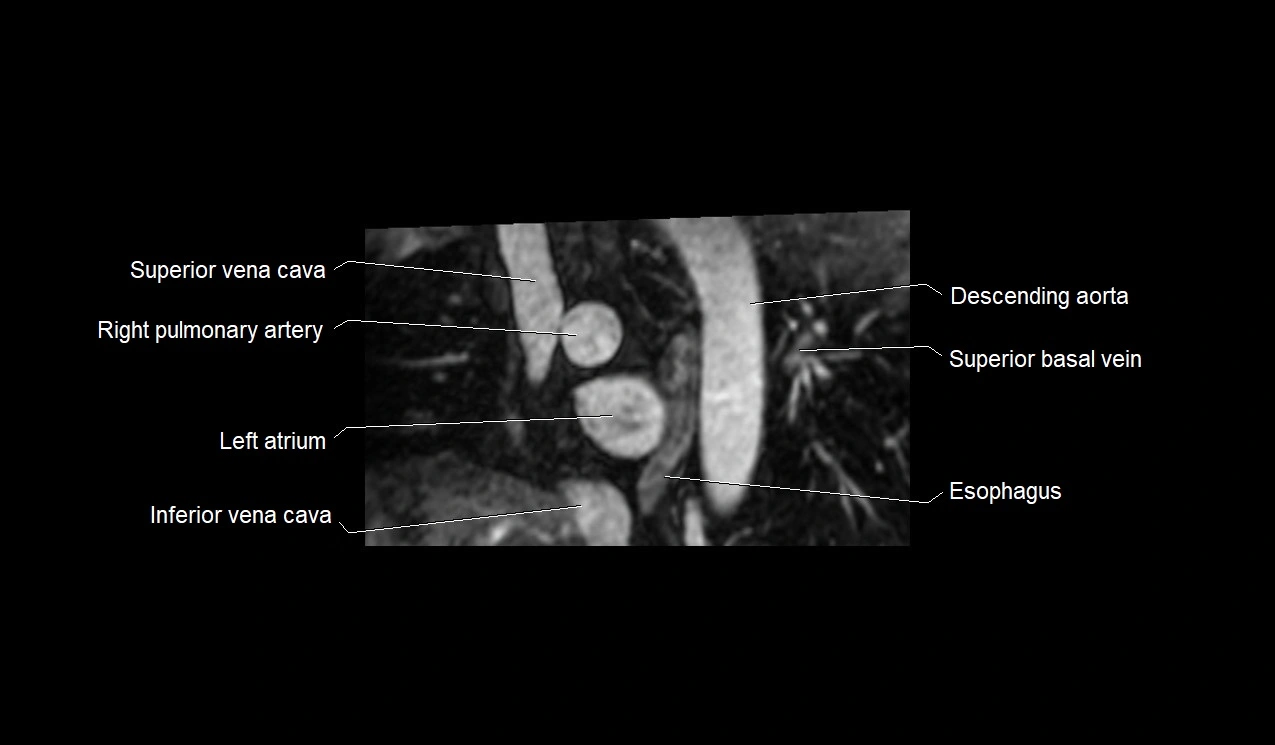

MRI image